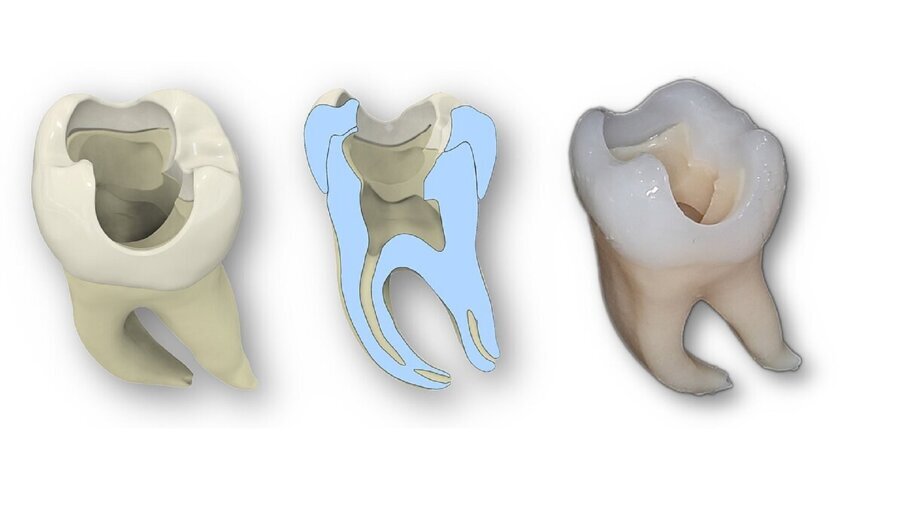

WÜRZBURG, Alemanha: Os avanços na tecnologia de impressão 3D têm o potencial de transformar a forma como os futuros dentistas aprendem habilidades práticas. Um novo estudo destacou o potencial de um modelo de molar impresso em 3D para aprimorar o treinamento endodôntico de estudantes de odontologia. Desenvolvido a partir de microtomografias computadorizadas de um dente humano extraído e fabricado com estereolitografia de alta resolução, o molar artificial replicou fielmente a anatomia complexa dos canais radiculares naturais e superou os blocos de acrílico convencionais, oferecendo uma ferramenta promissora para complementar e aprimorar os métodos tradicionais de treinamento.

De acordo com os resultados, os alunos avaliaram o dente impresso em 3D como significativamente superior aos blocos de acrílico em termos de adequação tanto para a prática quanto para o manuseio. Os pontos fortes comumente citados incluíram anatomia realista do canal radicular, consistência e reprodutibilidade entre os modelos, vantagens higiênicas e éticas em relação aos dentes naturais e menor custo unitário. Apesar desses benefícios, os dentes impressos ainda foram avaliados ligeiramente abaixo dos dentes naturais, principalmente em termos de realismo geral e adequação para a conclusão de todo o treinamento antes do tratamento dos pacientes.

Diante dos resultados, os pesquisadores concluíram que dentes de consultório impressos em 3D oferecem uma alternativa econômica, reprodutível e anatomicamente realista aos blocos de acrílico e modelos de dentes naturais no treinamento odontológico. Eles acreditam que melhorias adicionais, como a incorporação de anatomias variadas, características táteis aprimoradas ou tecido mole simulado, podem ajudar a diminuir a diferença entre modelos impressos e dentes naturais.